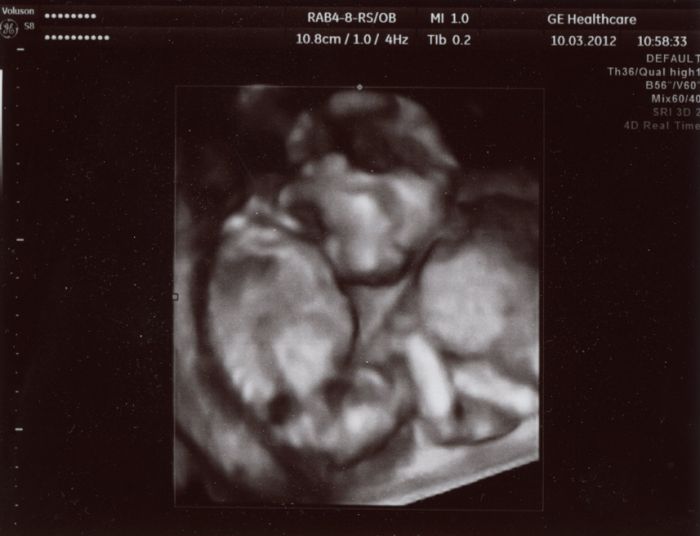

Tady je pár foteček. Video dostanu za 2 týdny až tam půjdu na kontrolu. Ten jeho přístroj mu to nedovede hned zpracovat, tak nám to video nemohl hned dát.